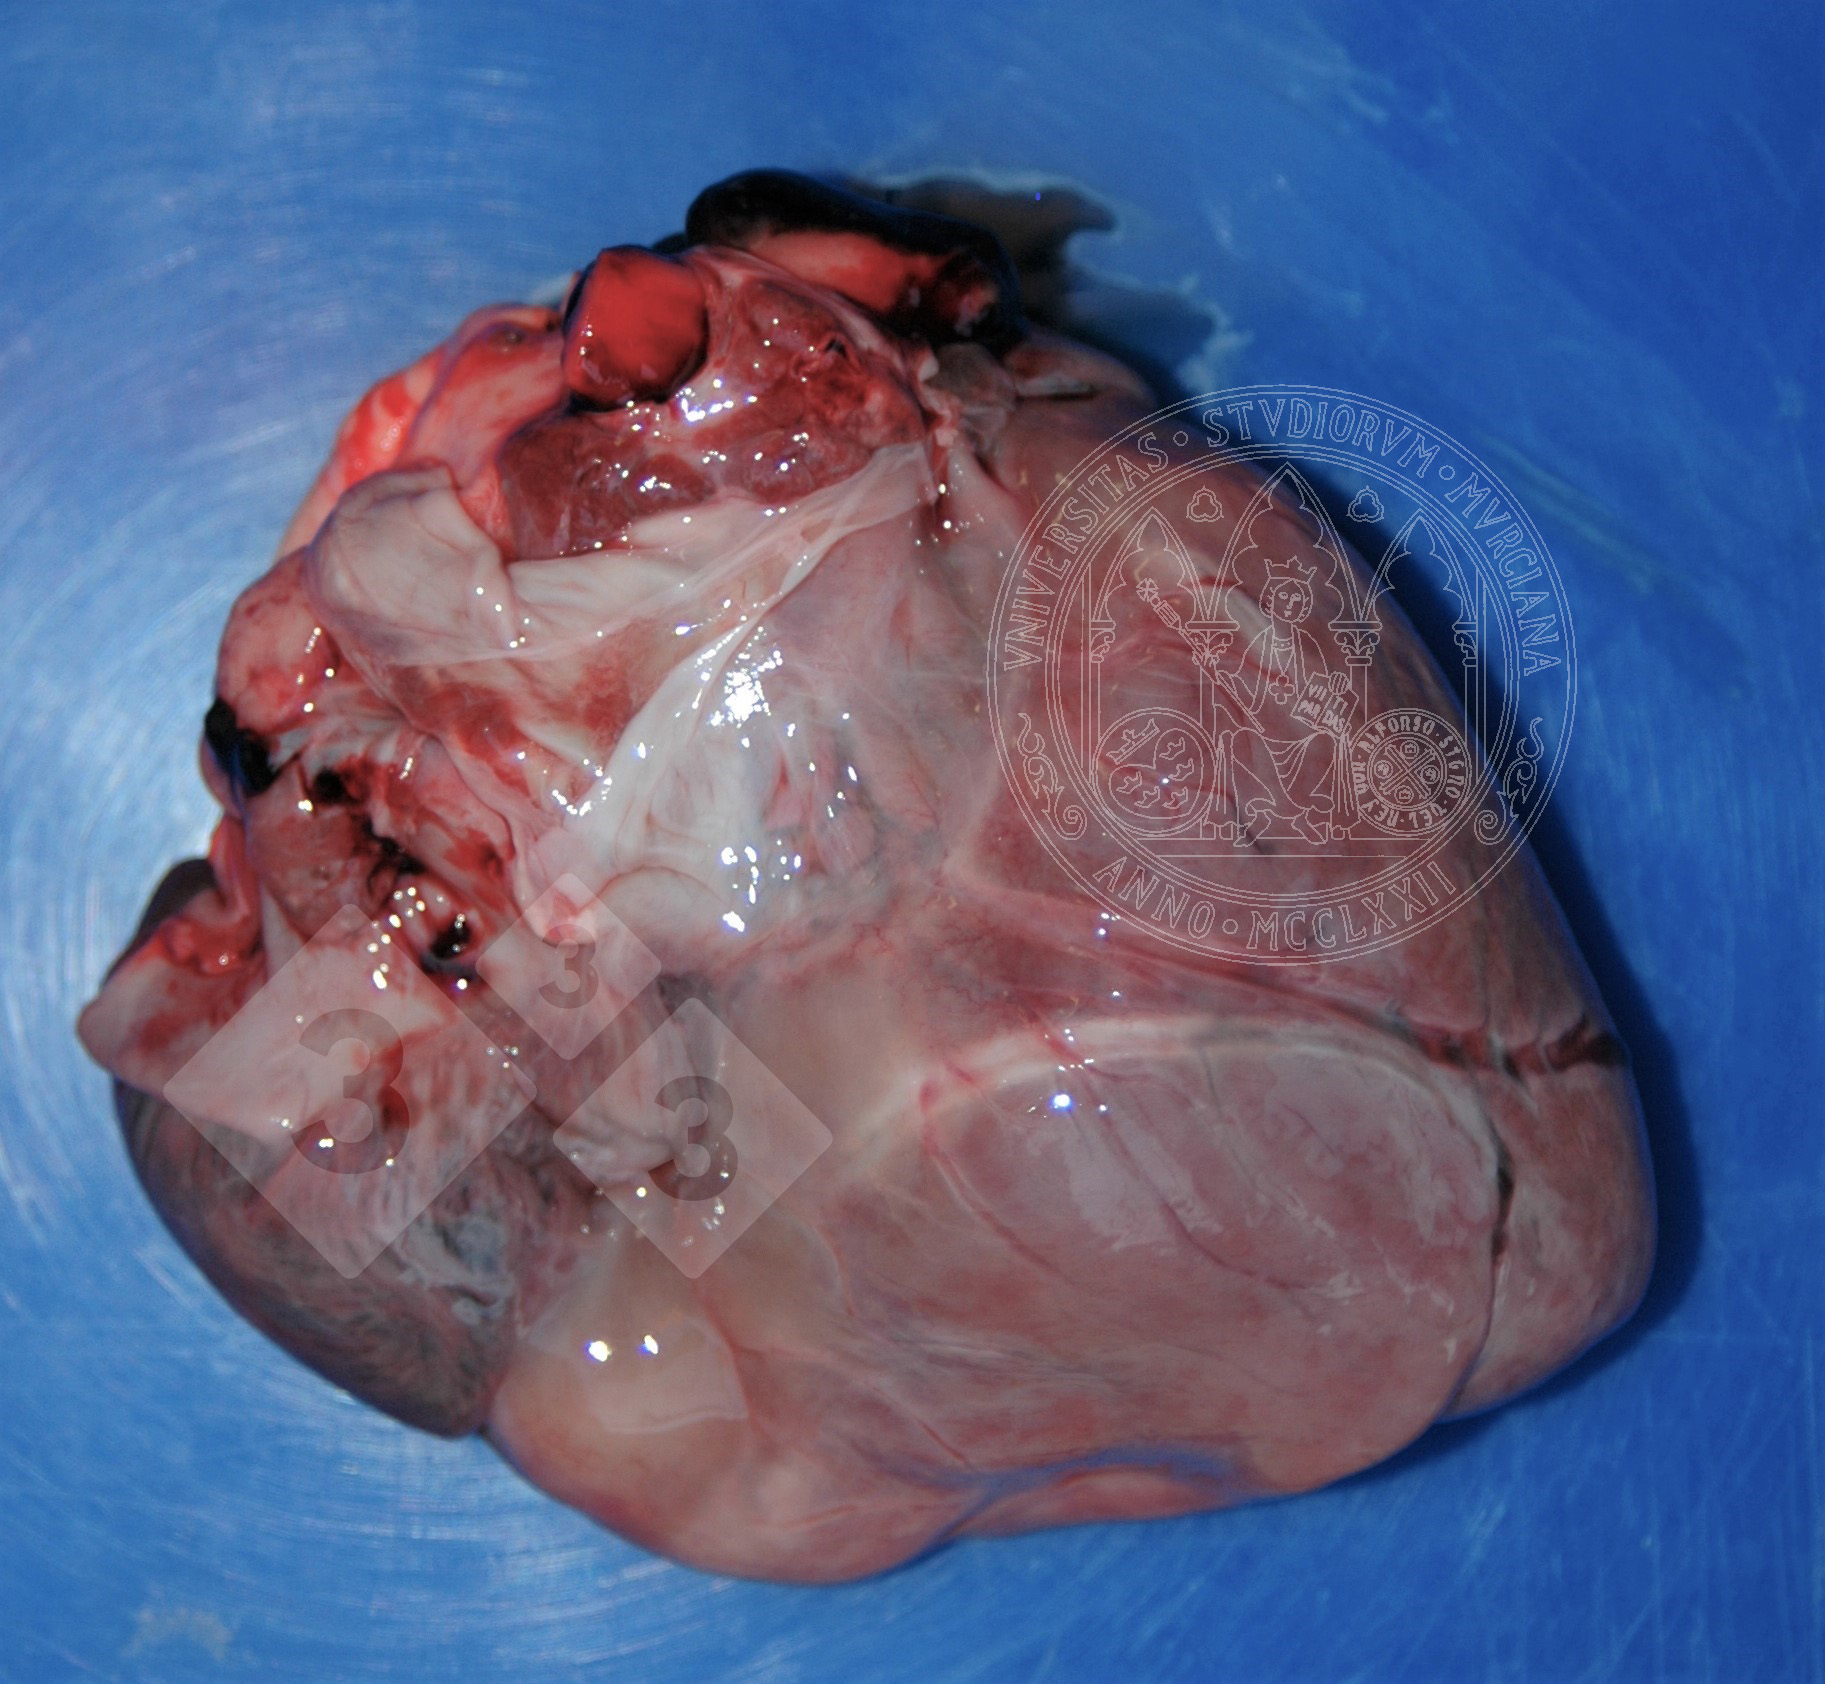

Possiamo osservare questa lesione negli stati di cachessia. Per vari motivi può esserci una mobilizzazione del grasso di deposito, come quella nell'epicardio. I vacuoli lipidici diminuiscono di dimensioni e sono sostituiti da un fluido proteinaceo, mentre aumentano il liquido interstiziale, acquisendo un aspetto gelatinoso grigiastro. A volte si possono vedere anche piccoli focolai bianchi di necrosi adiposa.

Dobbiamo fare diagnosi differenziale con edema, di origine infettiva o no.